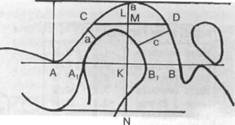

Рис. 13.32. Регистрация суставного пути и его запись на миллиметровой сетке.

1 — траектория суставного пути в виде кривой. Линия смещения оси суставной головки при перемещении нижней челюсти вниз совпадает с обратным движением; 2 — первые 5 мм кривой, соотнесенные к франкфуртской плоскости, образуют угол суставного пути.

пути смешения сустава осуществляют следующие действия: 1) регистратор устанавливают острием на отметке "О" координатной сетки при наиболее ретрузионном положении нижней челюсти пациента; 2) окончательно фиксируют удерживающие зажимы и пациента просят выдвинуть нижнюю челюсть вперед, чтобы проверить наличие регистратора на регистрационной площадке. После этого путь смещения сустава может быть записан при любых движениях нижней челюсти; 3) при произвольном максимальном перемещении пациентом нижней челюсти вниз регистрируют кривую движения суставной головки и диска по заднему скату суставного бугорка (рис. 13.32).